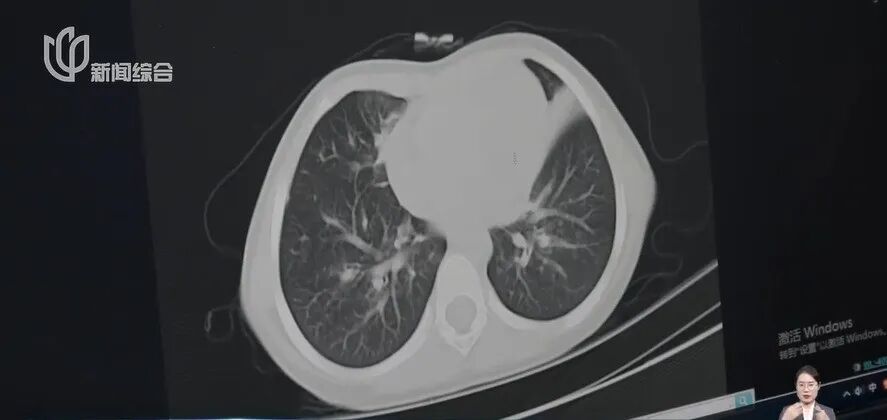

可导致肺炎、呼吸衰竭、脑炎等